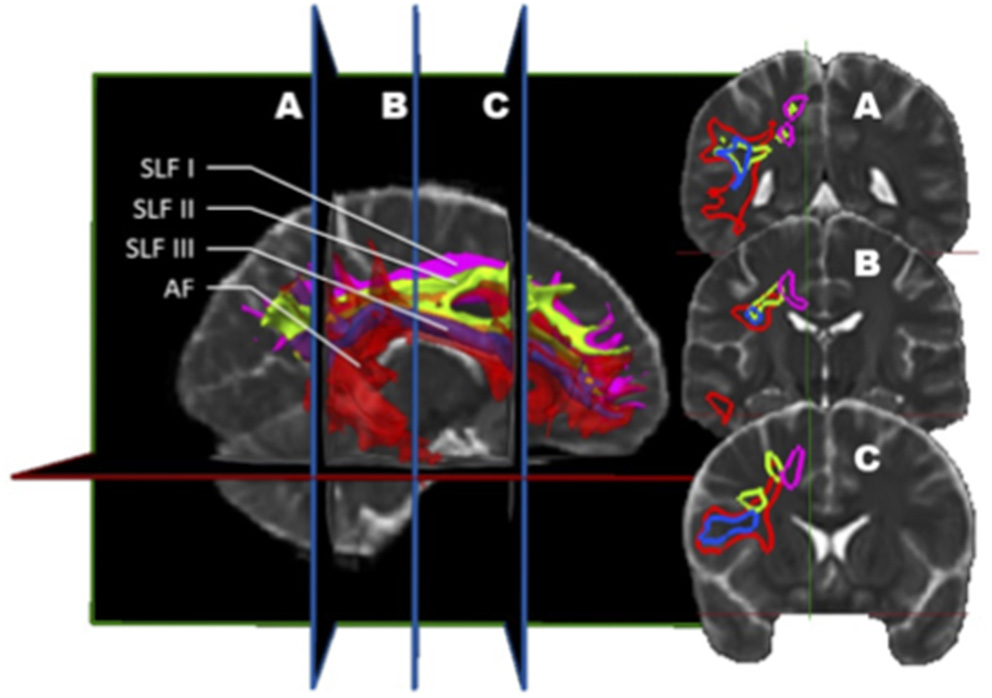

Figure 2

In vivo fiber tractography of the right SLF I (pink), SLF II (green), and SLF III (blue). A three-dimensional reconstruction of the three segments of the SLF is displayed at the left of the figure. The coronal sections of it (A, B, and C) are represented on the right. The dorso-ventral as well as medio-lateral localization of each sub-segment can be visualized on the coronal planes.